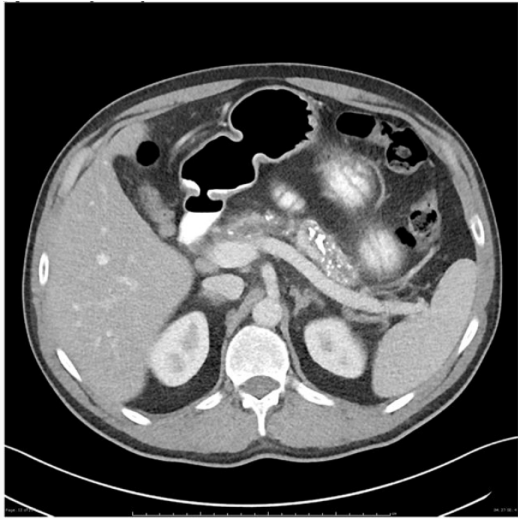

MSL, 55 anos, comparece ao hospital com quadro de dor abdominal, inespecífica, com piora após as alimentações, iniciada há cerca de

10 dias. Refere ser alcoolista crônico; porém, nega qualquer outra comorbidade. Realizada tomografia computadorizada de abdome,

como atesta a figura abaixo:

Figura 1 –Tomografia computadorizada de abdome.

Fonte: CPCON.

Qual seria a hipótese diagnóstica compatível com o caso apresentado e os achados de imagem que podem estar associados, além dos que são apresentados no exame?

Figura 1 –Tomografia computadorizada de abdome.

Fonte: CPCON.

Qual seria a hipótese diagnóstica compatível com o caso apresentado e os achados de imagem que podem estar associados, além dos que são apresentados no exame?